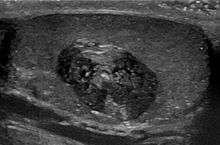

An epidermoid cyst is a benign cyst usually found on the skin. The cyst develops out of ectodermal tissue. Histologically, it is made of a thin layer of squamous epithelium.

Epidermoid cysts are usually diagnosed when a person notices a bump on their skin and seeks medical attention. The definitive diagnosis is made after excision by a pathologist based on microscopic appearance of a cystic lesion lined by cornified epithelium containing lamellated keratin without calcifications. They can also be seen as isointense lesions on MRI or hyperintensities on FLAIR.